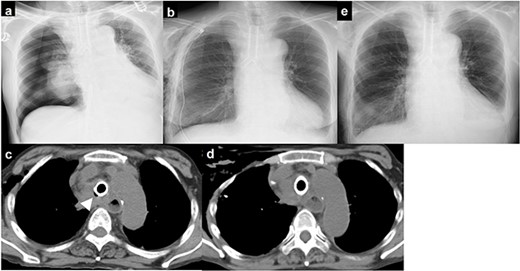

(a) chest X-ray showing right pneumothorax; (b) chest drainage was performed; (c) chest computed tomography immediately after surgery showing an air space on the right side of the stent; (d) the air space on the right side of the stent gradually disappeared; (e) chest X-ray showing no recurrence of pneumothorax.

Chest computed tomography immediately after surgery showed an air space on the right side of the stent (Fig. 3c). The space gradually disappeared over time, and no air leakage was observed (Fig. 3d). The chest drain was removed on postoperative Day 12, and there was no recurrence of pneumothorax (Fig. 3e).